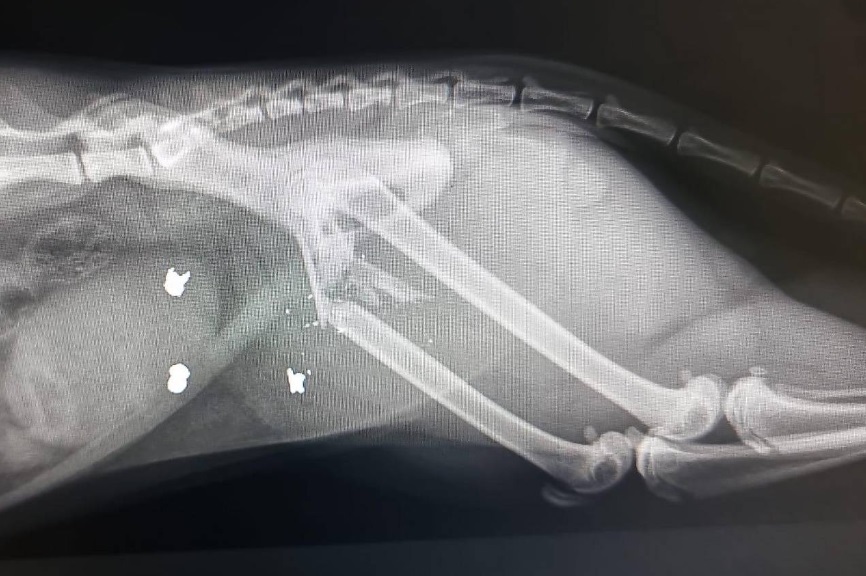

Polise göre, kimliği belirsiz failler Pazar günü saat 11.00 ile 19.00 arasında Dornbirn'in merkezinde bir erkek kediye havalı tüfekle ateş etti. Kedicik "Leo "nun arka bacağında parçalı bir kırık meydana geldi ve bir veteriner tarafından ameliyat edilmesi gerekti.